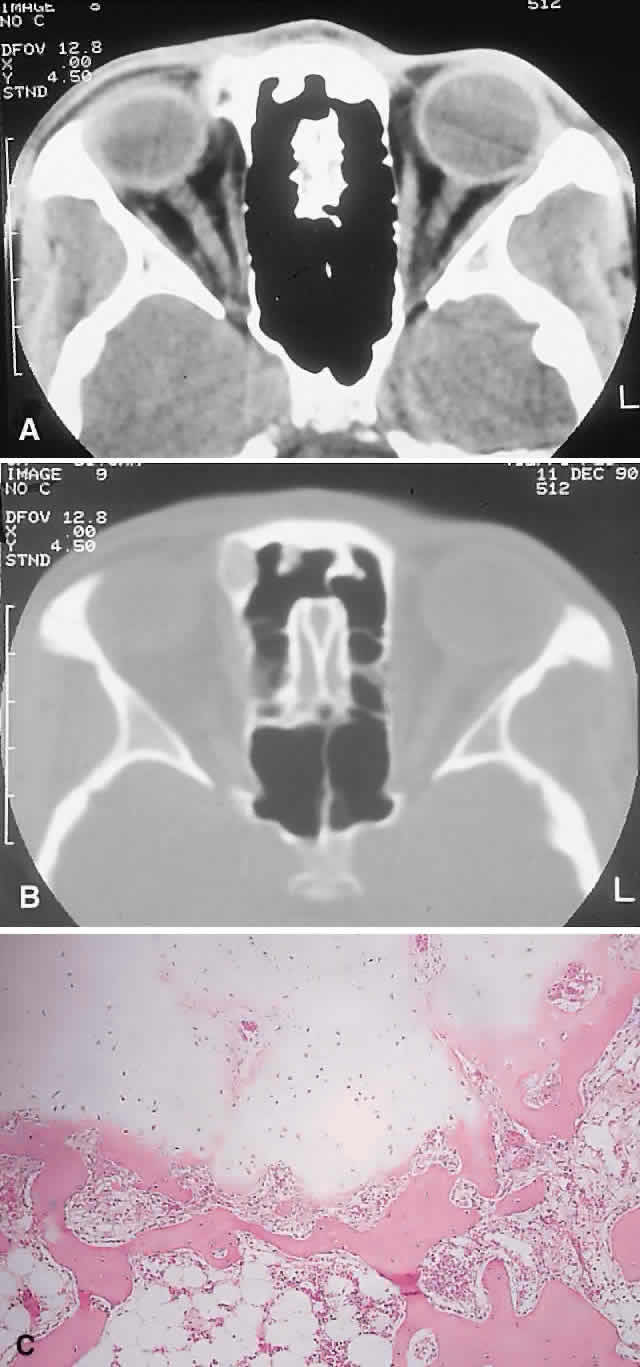

PRESENTATION. The site and the extent of disease are the major determinants of symptomatology. Facial asymmetry, proptosis, and globe displacement evolving over many years are the most common manifestations (Fig. 2). Nasolacrimal duct blockage, diplopia, nasal obstruction, malocclusion, raised intracranial pressure, and cranial nerve palsies also occur.25,28–30 Acute or subacute compressive optic neuropathy can arise as a result of intralesional hemorrhage, sphenoidal mucocele, or secondary aneurysmal bone cyst.31 A more chronic visual loss, although less commonly reported, may occur as a result of compression in the optic canal or at the chiasm. On occasion, a superimposed ischemic neuropathy in the context of chronic compression leads to an acute on chronic deterioration in vision.32

Fig. 2. A. A 20-year-old man presented with a longstanding history of left proptosis and facial asymmetry. B and C. Bone window CT scan showed extensive fibrous dysplasia involving the greater wing of the sphenoid in a sclerotic fashion and a more pagetoid appearance in the maxillary and ethmoidal regions. D and E. Dominant histologic features consisted of irregular trabeculae of woven bone in a fibrous stroma with minimal osteoblastic activity (E) surrounding the osteoid (hematoxylin-eosin; D × 20, E × 50).

IMAGING. In the craniofacial bones, fibrous dysplasia tends to expand the bone, with thinning of the overlying cortex. The margins are poorly defined, and the dysplasia transgresses suture lines; the proportion of mineralized to fibrous tissue determines the degree of radiolucency. Most cases demonstrate a relatively equal mixture, resulting in a pagetoid appearance. Where the fibrous element is predominant, there may be cystlike areas; a preponderance of mineralized tissue, however, results in a homogeneous, sclerotic, “ground-glass” picture. Fries34 reviewed 39 patients with fibrous dysplasia of the craniofacial bones and found a pagetoid pattern to be most common (56%), followed by sclerotic (23%) and cystlike (21%) appearances.

HISTOPATHOLOGY. Macroscopically, fibrous dysplasia consists of gritty, white-to-pink tissue, often with blood or serous-filled cystic areas. Histologically, there is a fibrous background containing trabeculae of woven bone. The stroma has variable amounts of collagen, fibroblasts, and vascularity. There may also be myxomatous areas and secondary aneurysmal bone cysts. The curvilinear bone trabeculae take on a variety of configurations, including C or Y shapes (so-called Chinese characters). These trabeculae sometimes have irregular margins as a result of the attachment of collagen fibers arising in the stroma. Cartilaginous nodules as well as small foci of lamellar bone are occasionally seen, but the vast majority of lesions contain immature woven bone. At its periphery, fibrous dysplasia permeates normal bone, and there may be areas of reactive bone with more prominent lamellar bone formation and osteoblastic rimming. Sequential biopsies of fibrous dysplasia from childhood to adult life have shown that the histologic picture does not change with time.36